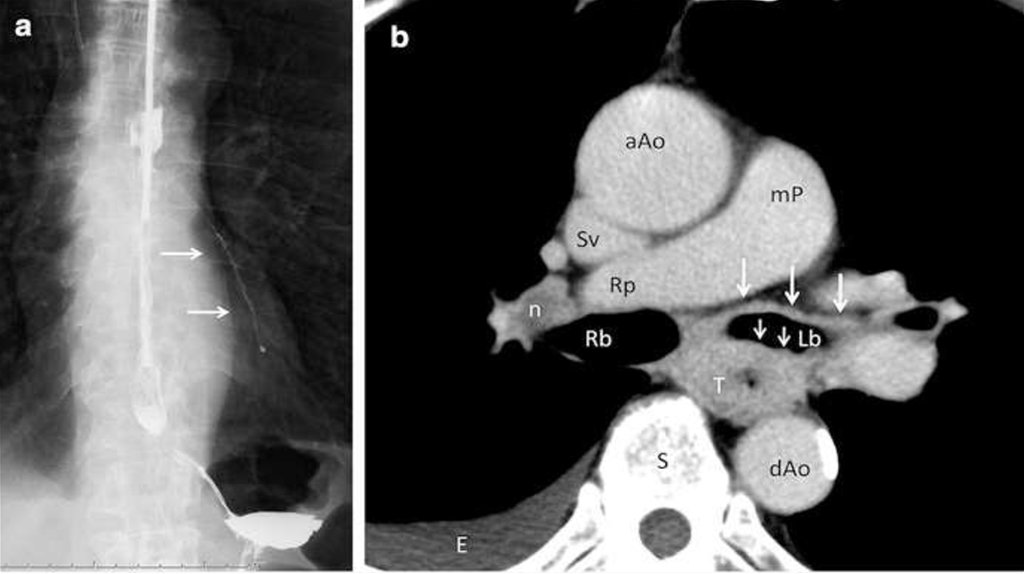

Пациенту выполнено рентгенологическое исследование пищевода и КТ области грудной

клетки (снимки прилагаются).

1. Рак пищевода среднегрудного отдела. Бронхо-пищеводный свищ (инвазия в

бронх, видна полоса затекания контраста в левый главный бронх).

2. Т4b – инвазия в главный бронх